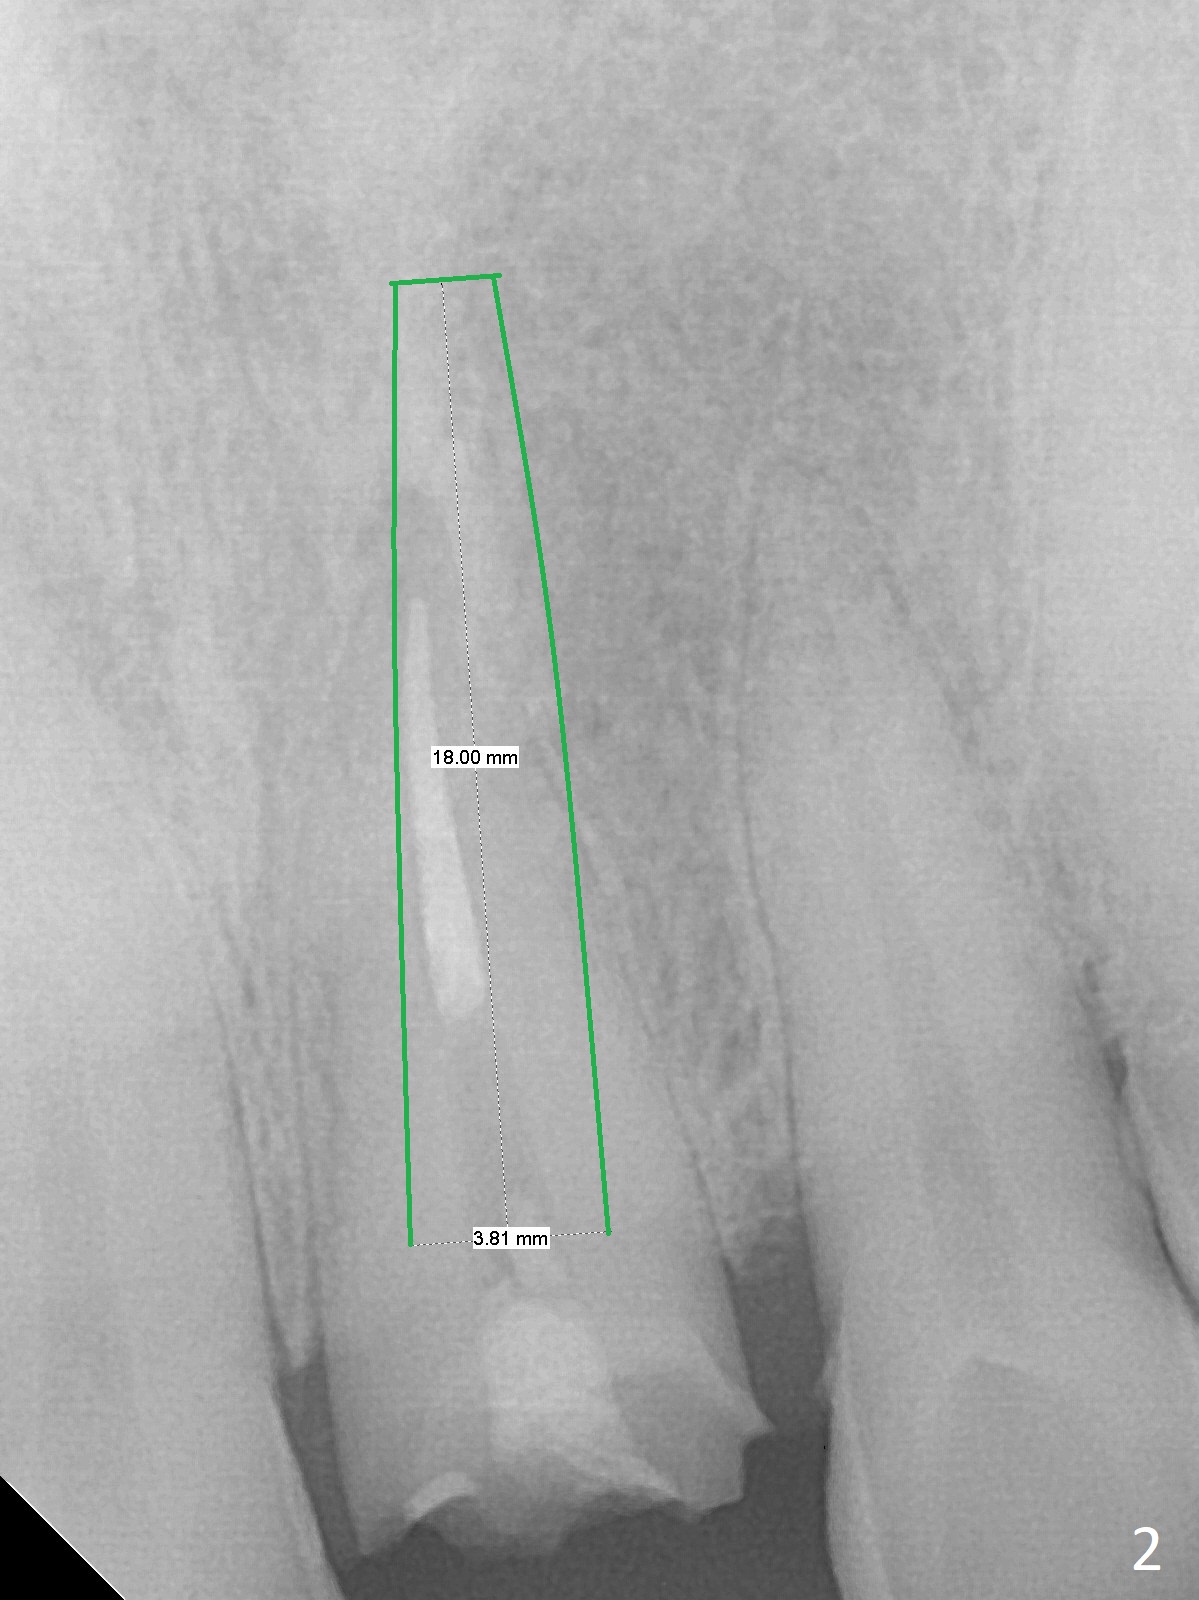

After breaking and dislodging the crown at #9, a 57-year-old man fractures the tooth (Fig.1). The teeth # 3 and 19 have cusp fracture or severe wear, indication for crowns. Since there is anterior deep bite, the implant should be long for primary stability (Fig.2). To avoid the Incisive Canal (*), start osteotomy distal. The initial depth will be 21 mm. After trying a 3.8x15 mm dummy implant with good trajectory, increase the osteotomy for larger implant (4.0 or 4.5 mm) to reduce chance of implant breakage due to heavy mastication.